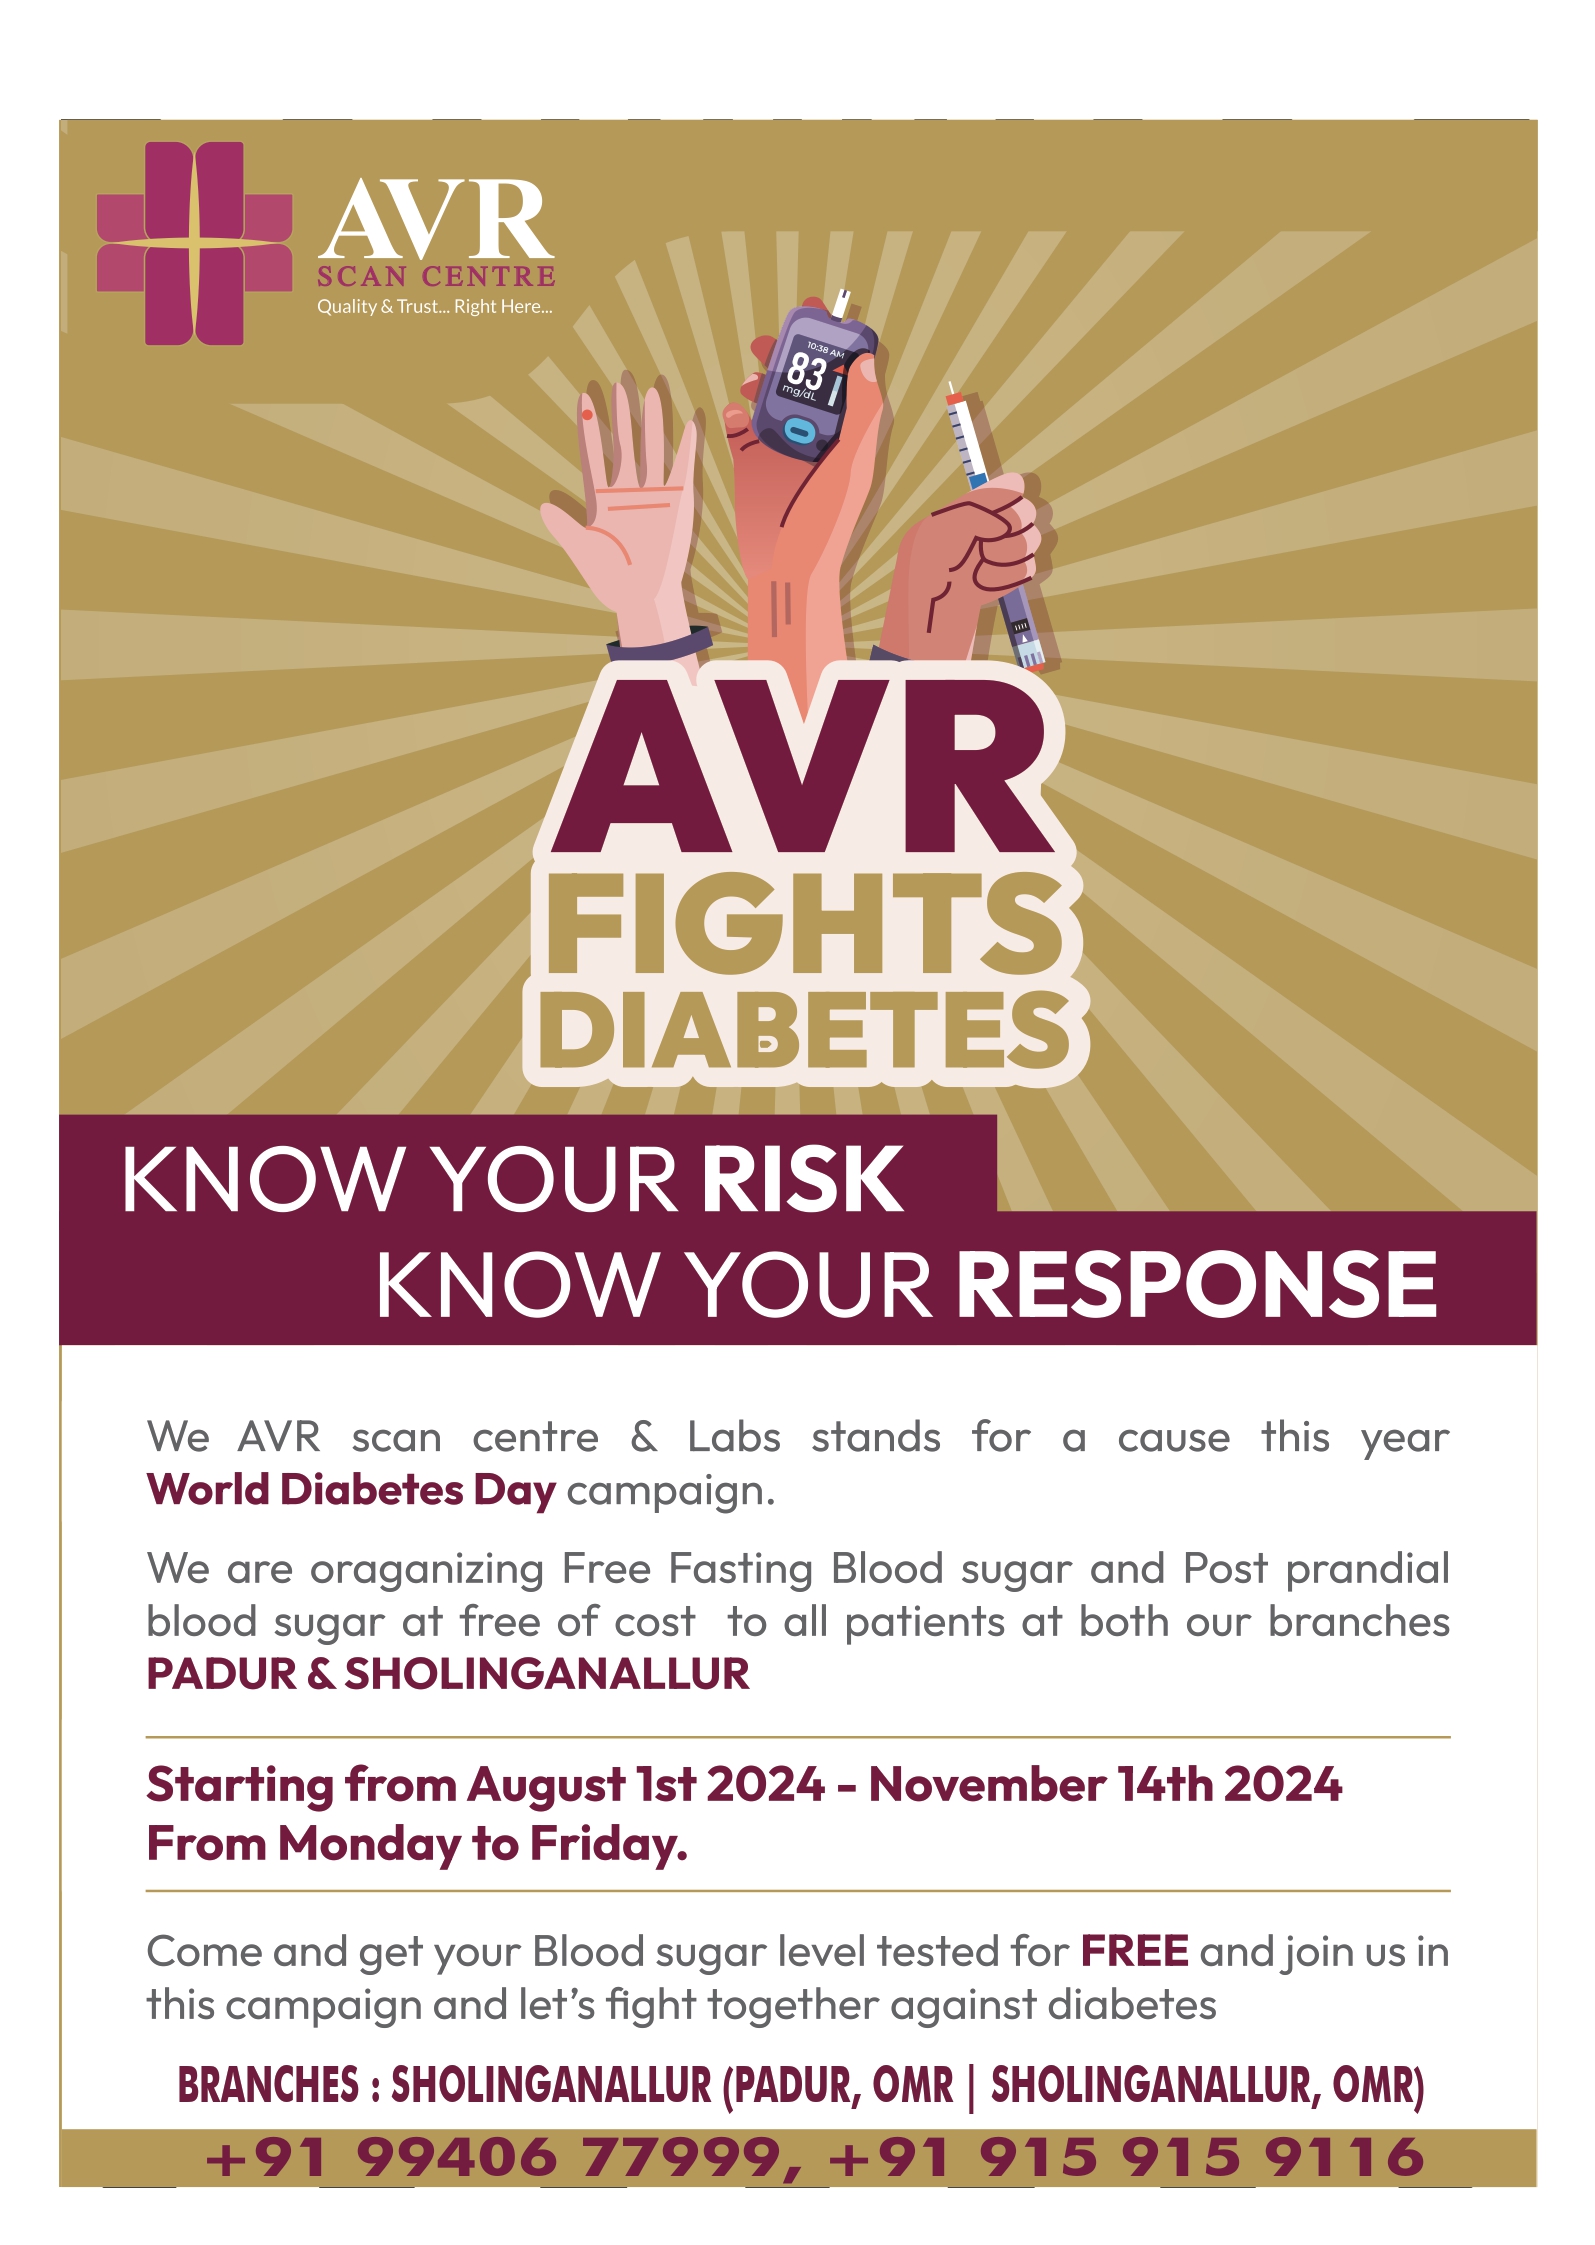

Welcome to AVR Scan

Our doctors are on call 24/7. Same Day Appointments Available.